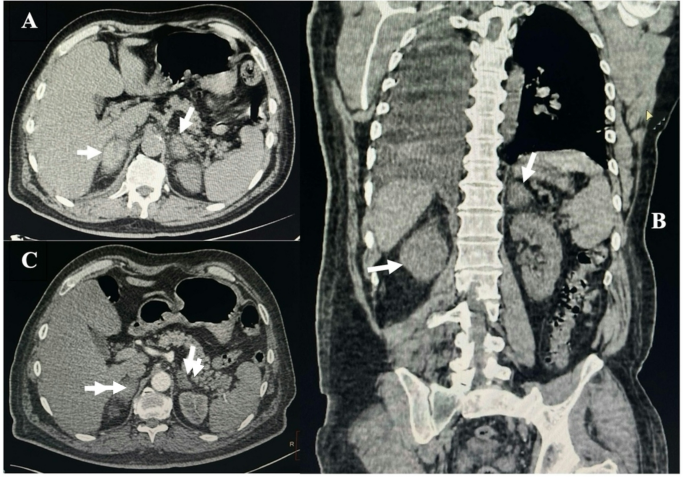

CT结果显示双侧肾上腺显著增大(右侧:28×42毫米;左侧:23×24毫米),密度不均,渗出物延伸至肾周和肾旁间隙以及相邻的腹膜后结构,符合双侧肾上腺出血(BAH)的表现(图1)。

计算机断层扫描(CT)显示双侧肾上腺出血。横向(A)和冠状(B)视图显示肾上腺显著增大,箭头所示。C)随访CT(10天后)显示血肿大小显著减小(箭头所示)

皮质醇和促肾上腺皮质激素(ACTH)水平分别为124.7纳米摩尔(正常值:222–690纳米摩尔/升)和81.5纳米摩尔/升(正常值:7.2–63.3纳克/升)。患者开始静脉注射氢化可的松,剂量为每天两次,每次100毫克。症状改善后,改为口服氢化可的松(每天两次,每次20毫克),同时继续服用氨氯地平、β受体阻滞剂和维生素K拮抗剂。